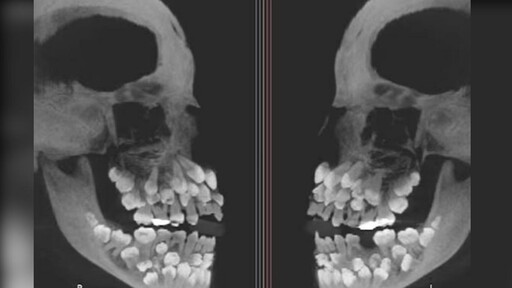

圖/巴西女童擁有81顆牙齒嚇壞醫師。(翻攝 朝鮮日報)

據《朝鮮日報》報導,《VN Express》等外媒15日報導,這名來自巴西米納斯吉拉斯州的女孩,日前因為想拔除一顆上排乳牙而到醫院就診,但在拍攝X光後,醫師意外發現她口中竟藏有18顆乳牙、32顆恆牙,以及31顆多生牙,總數多達81顆。

一般成人的正常牙齒數量為32顆,超過正常數量額外長出的牙齒被稱為「多生牙」,通常多生牙是1至2顆,像該名巴西女童如此多的多生牙相當罕見。多生牙通常潛藏在牙齦內,可能阻礙正常牙齒或造成牙齒排列混亂,甚至引發囊腫等其他問題。